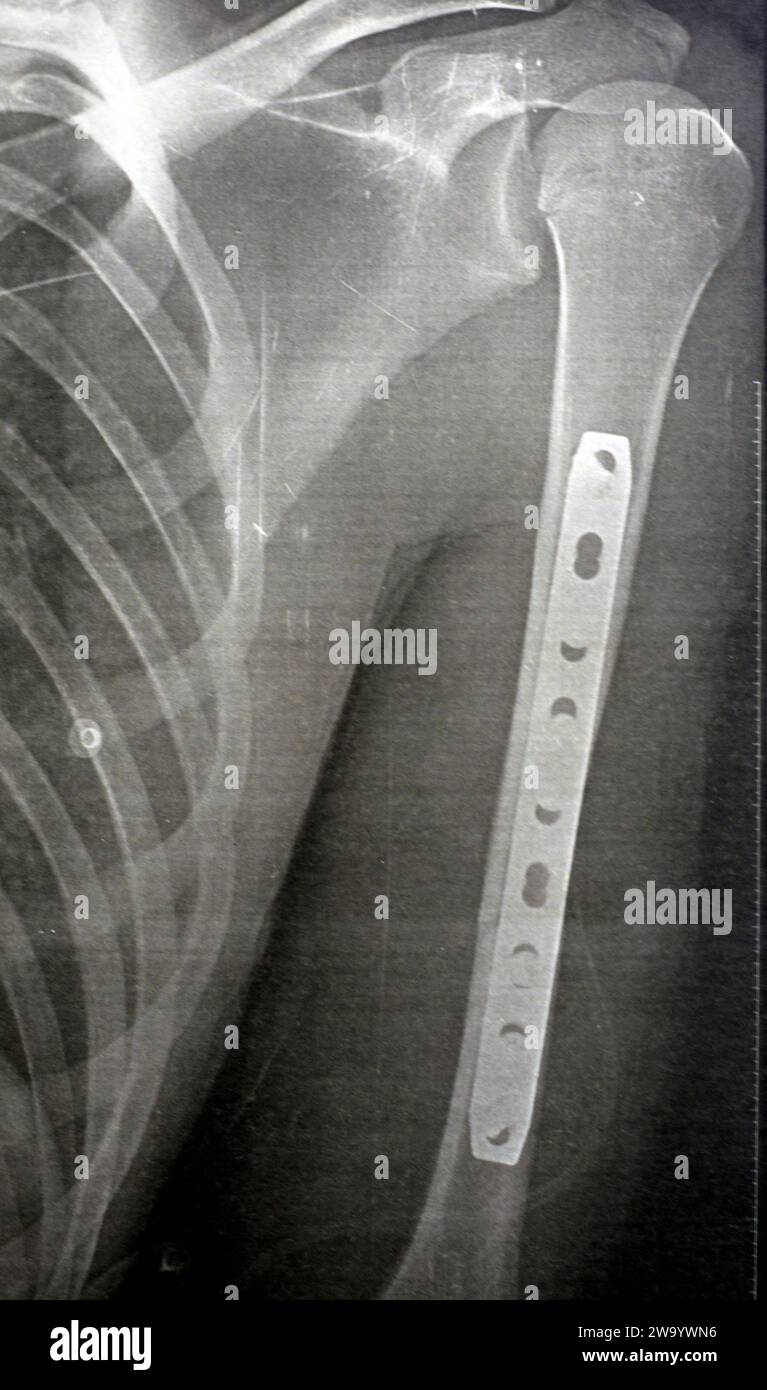

RF2WA30RC–Radiografia semplice che mostra frattura dell'omero sinistro dell'albero intermedio trasversale causata da un trauma diretto in un incidente stradale, gestito da riduzione aperta e fissa interna

RF2W9YW73–Radiografia semplice che mostra frattura dell'omero sinistro dell'albero intermedio trasversale causata da un trauma diretto in un incidente stradale, gestito da riduzione aperta e fissa interna

RF2WA2Y85–Radiografia semplice che mostra frattura dell'omero sinistro dell'albero intermedio trasversale causata da un trauma diretto in un incidente stradale, gestito da riduzione aperta e fissa interna

RF2W9YWMX–Radiografia semplice che mostra frattura dell'omero sinistro dell'albero intermedio trasversale causata da un trauma diretto in un incidente stradale, gestito da riduzione aperta e fissa interna

RF2W9YW6Y–Radiografia semplice che mostra frattura dell'omero sinistro dell'albero intermedio trasversale causata da un trauma diretto in un incidente stradale, gestito da riduzione aperta e fissa interna

RF2W9YWN6–Radiografia semplice che mostra frattura dell'omero sinistro dell'albero intermedio trasversale causata da un trauma diretto in un incidente stradale, gestito da riduzione aperta e fissa interna